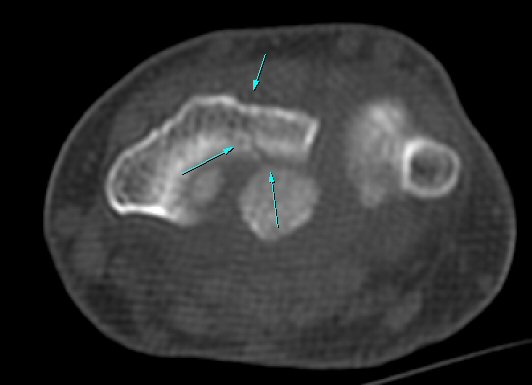

¿ä°ñ Ⱦ´Ü¸é°Ë»ç¿¡¼­ lister's tubercle ̫̿¿¡¼­ ÇÇÁú°ñ ¿¬°á¼º ¼Ò½Ç(loss of cotical continuity)ÀÌ °üÂûµÊ(»çÁø 4).